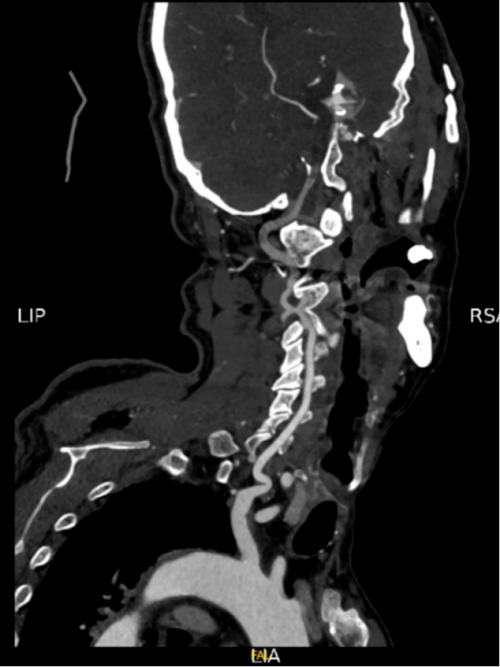

11月17日急诊辅助检查:CTA:颅脑、颈部动脉粥样硬化改变。基底动脉、左侧推动脉V4段远端闭塞。左侧大脑后动脉P2段管腔中度狭窄。建议:DSA。颅脑CTP提示脑干及两侧小脑半球部分区域灌注减低。多发脑梗塞。建议:MRI检查(含DWI)。

患者急性昏迷起病,发病时伴随呕吐,考虑存在吸入性肺炎,予经验性抗生素治疗,留取病原学检查,并完善胸部CT证实两肺下叶渗出性炎性表现,患者体温逐渐升高,最高38.9℃,血气分析提示氧合下降,术后脱机延迟。